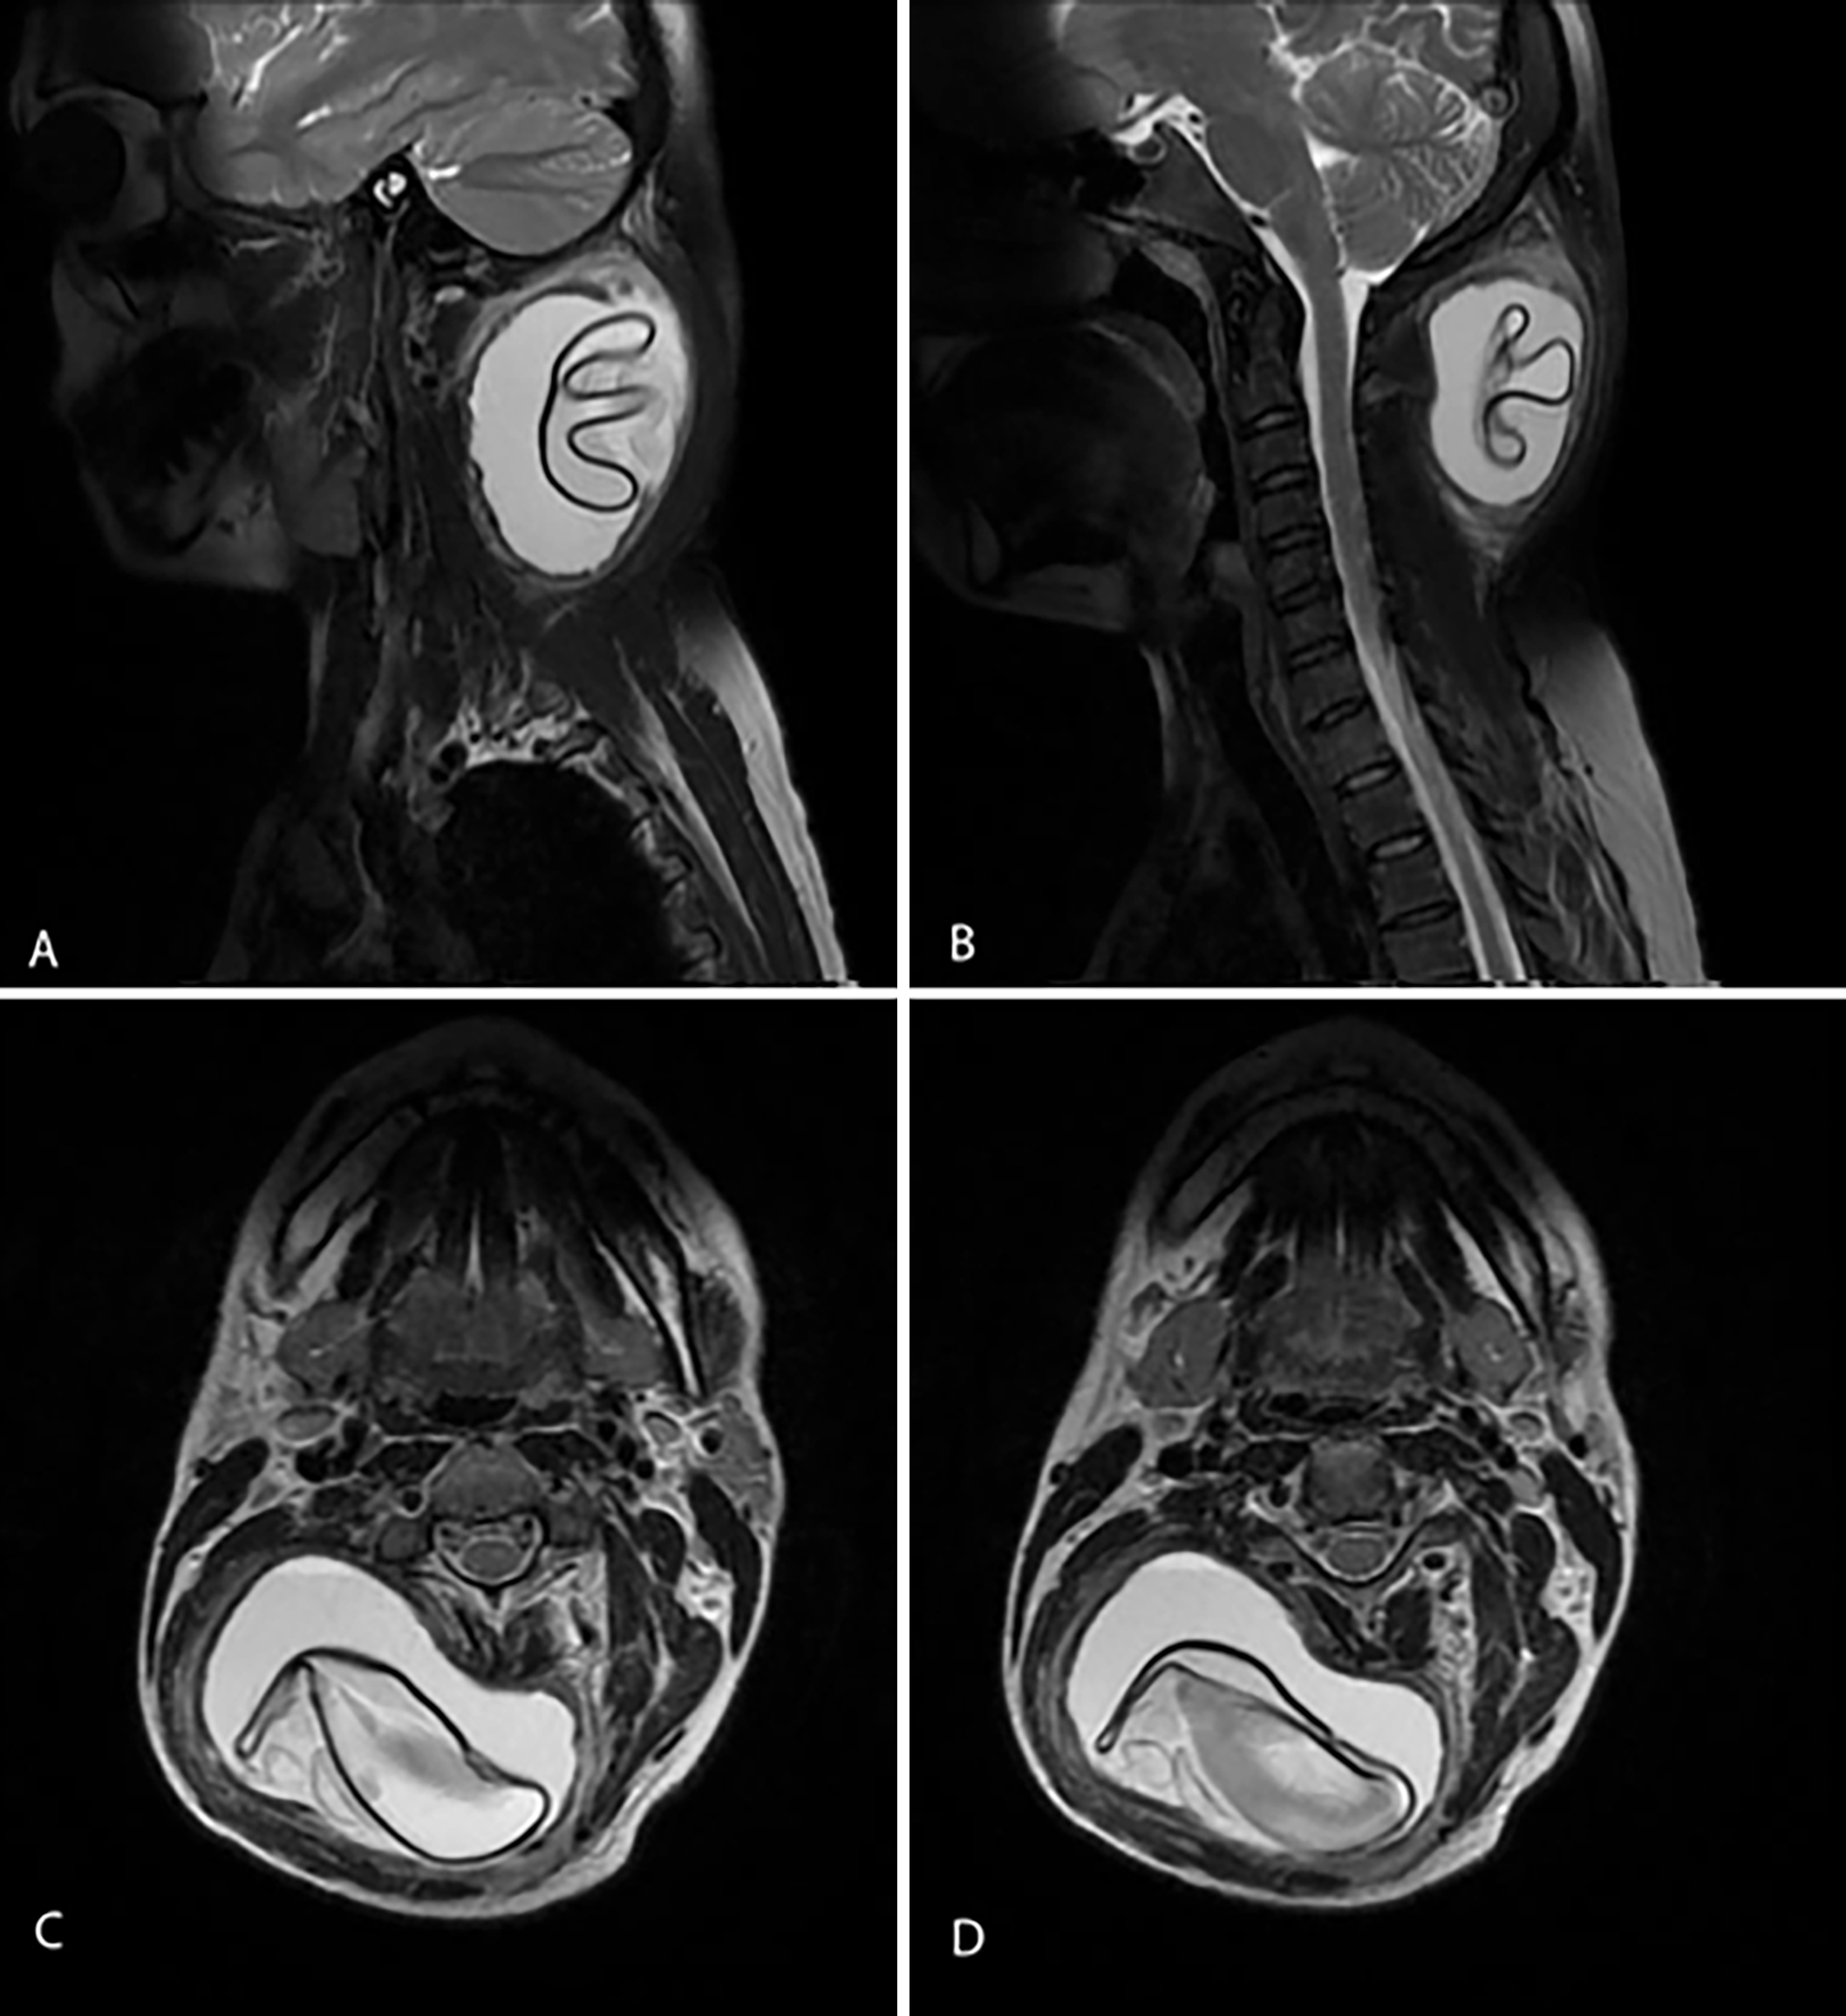

Magnetic resonance imaging (MRI) of the neck revealed a well-defined, round-to-oval cystic lesion with abnormal signal intensity, and an internal detached floating membrane within the soft tissues of the right neck region. The lesion extended into the right paraspinal area from the C1 to C4 vertebral levels. It demons- trated iso-intense signal on T1-weighted imaging (T1WI) and hyperintense signal on T2-weighted imaging (T2WI), with patchy areas of restricted diffusion on diffusion-weighted imaging (DWI) and corresponding low signal intensity on apparent diffusion coefficient (ADC) mapping. Post-contrast sequences showed peripheral enhancements without surrounding oedema. The lesion measured approximately 4.4 × 7.2 cm (anteroposterior × transverse) on axial T2WI and 6.9 cm craniocaudally on coronal T2WI. Posterolaterally, it displaced the splenius capitis, semispinalis capitis, longissimus capitis, and trapezius muscles on the right side; anteromedially, it compressed and displaced the right oblique capitis inferiorly; and medially, it displaced the ligamentum nuchae towards the left (Figure 2 and 3). The diagnosis was confirmed by  a  positive  Echinococcus  antibody  titre.

Figure 3: Post-contrast T1-weighted sagittal (A, B) and coronal (C, D) MRI images of the neck showing a well-defined, round-to-oval cystic lesion with an internal detached floating membrane within the soft tissues of the right neck, demonstrating peripheral contrast enhancement.